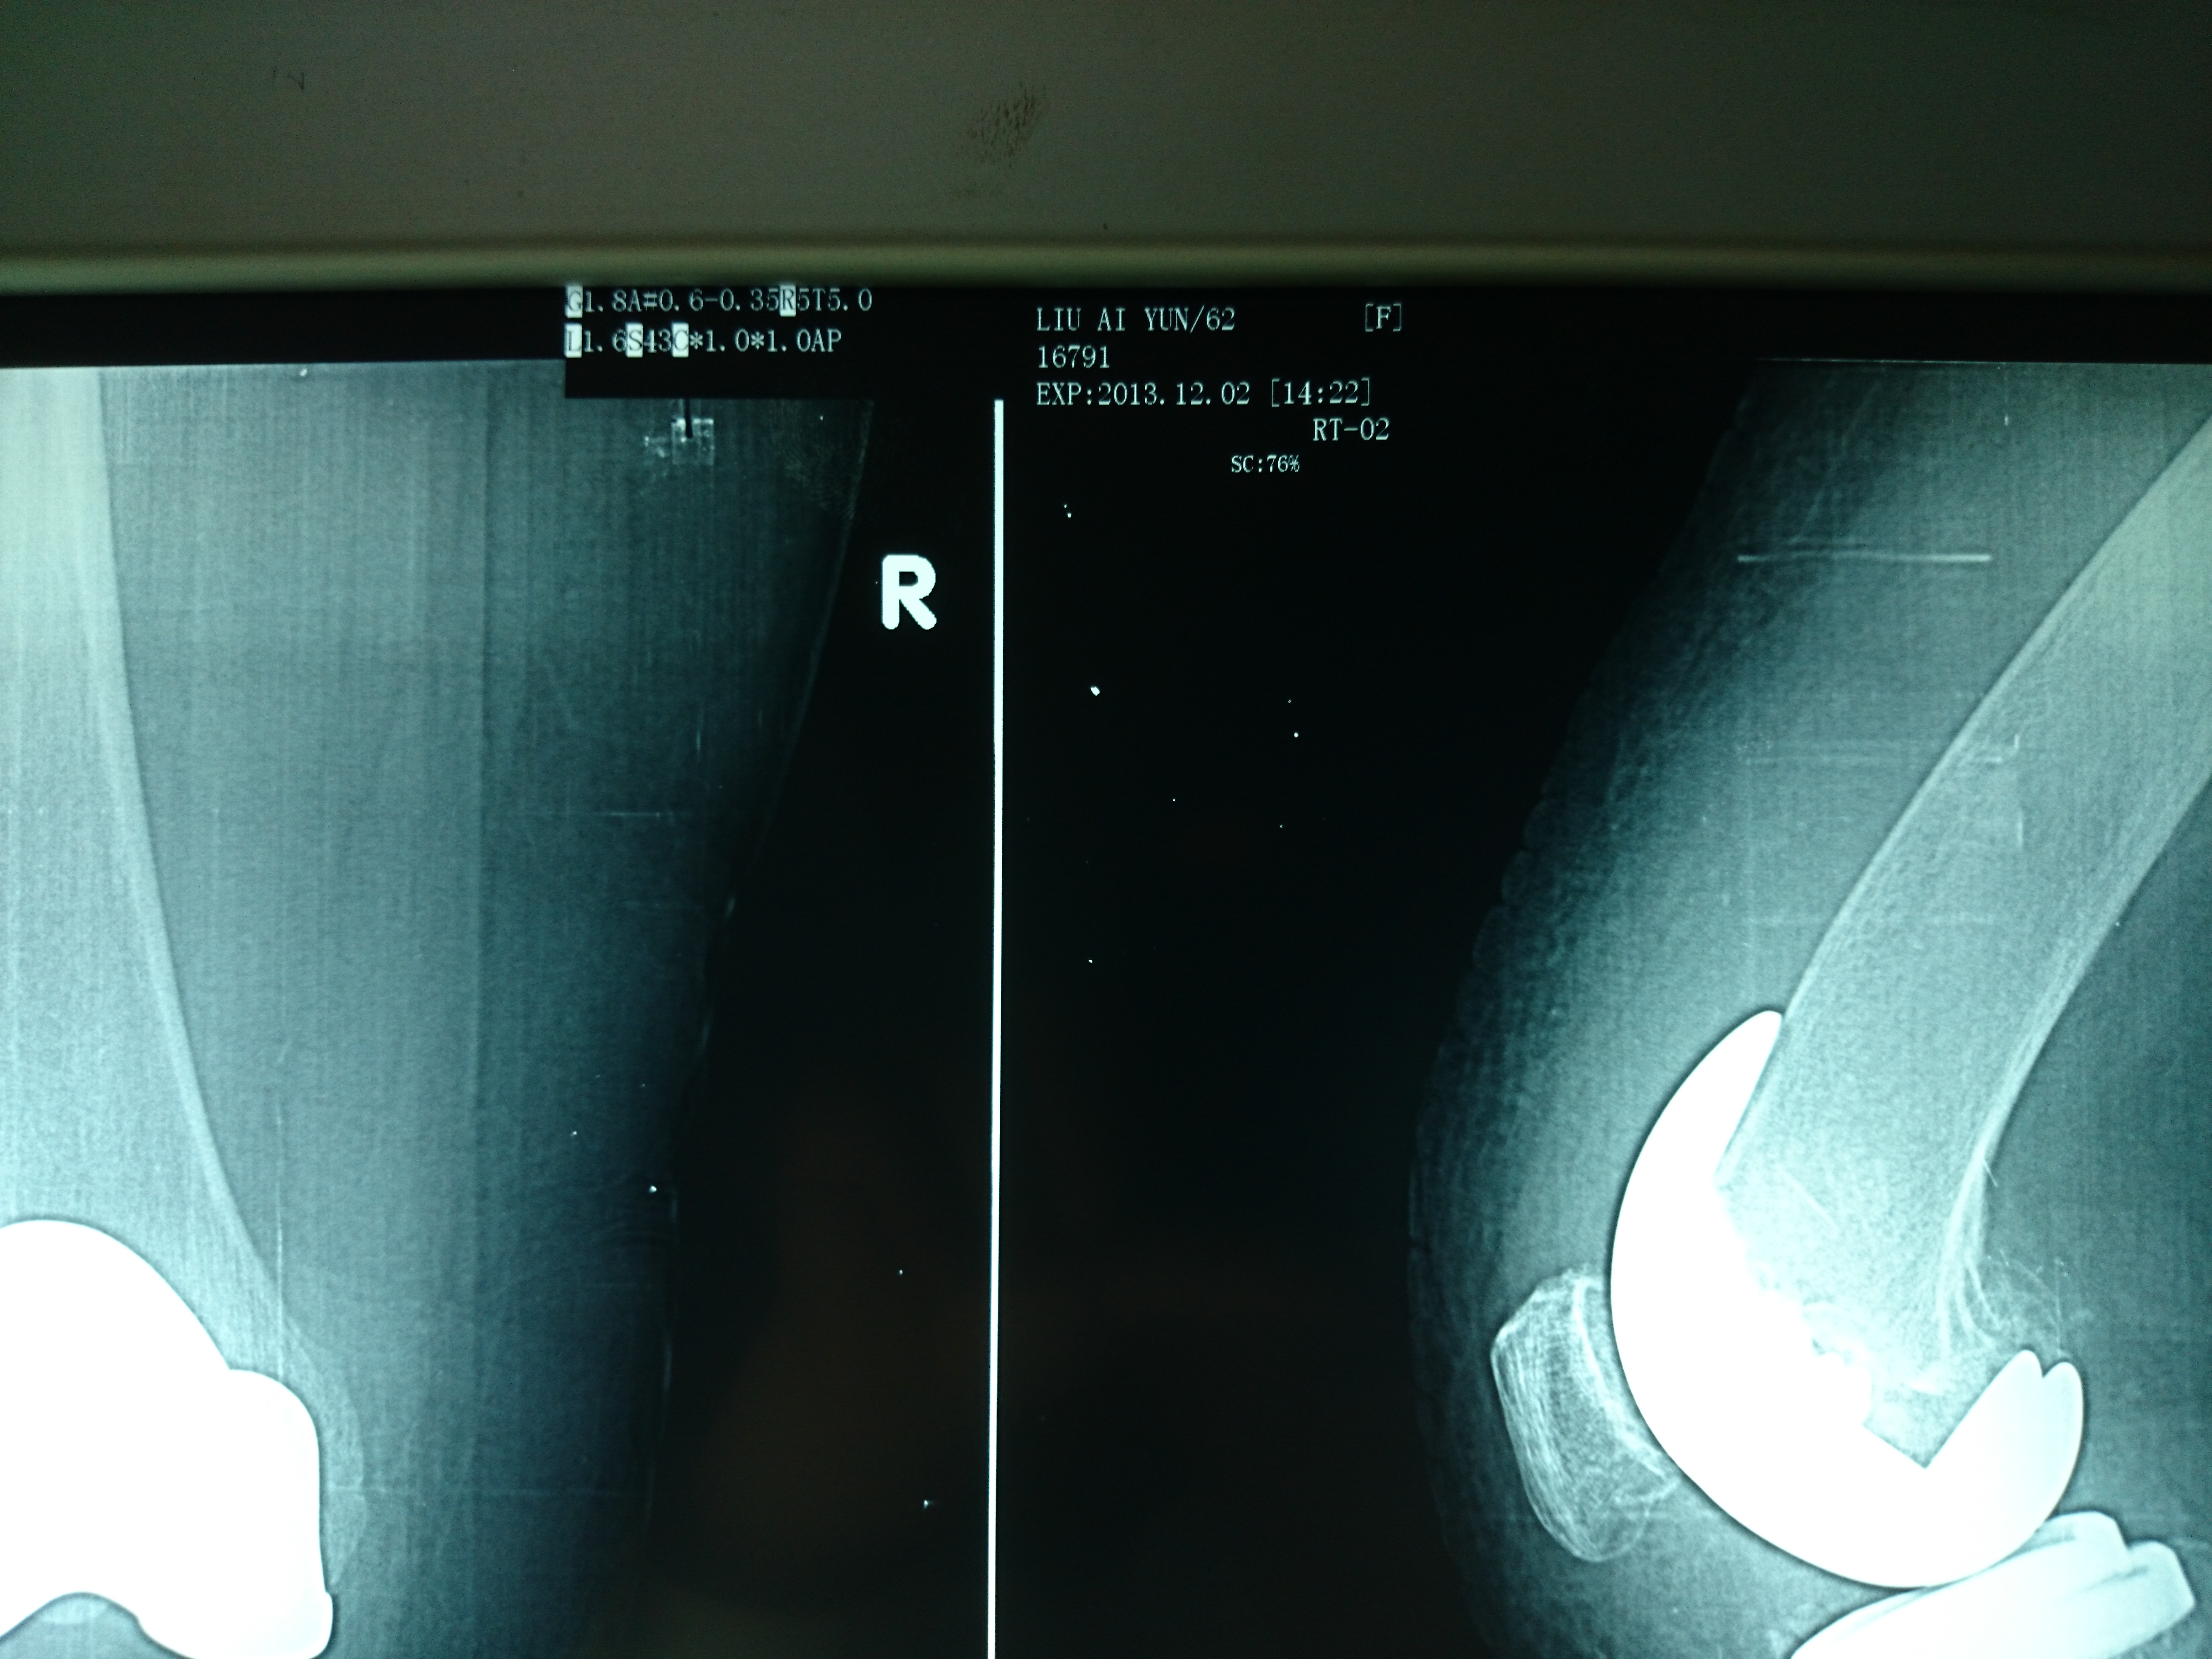

首页 > 张恒云工作室 > 影像资料 二十三